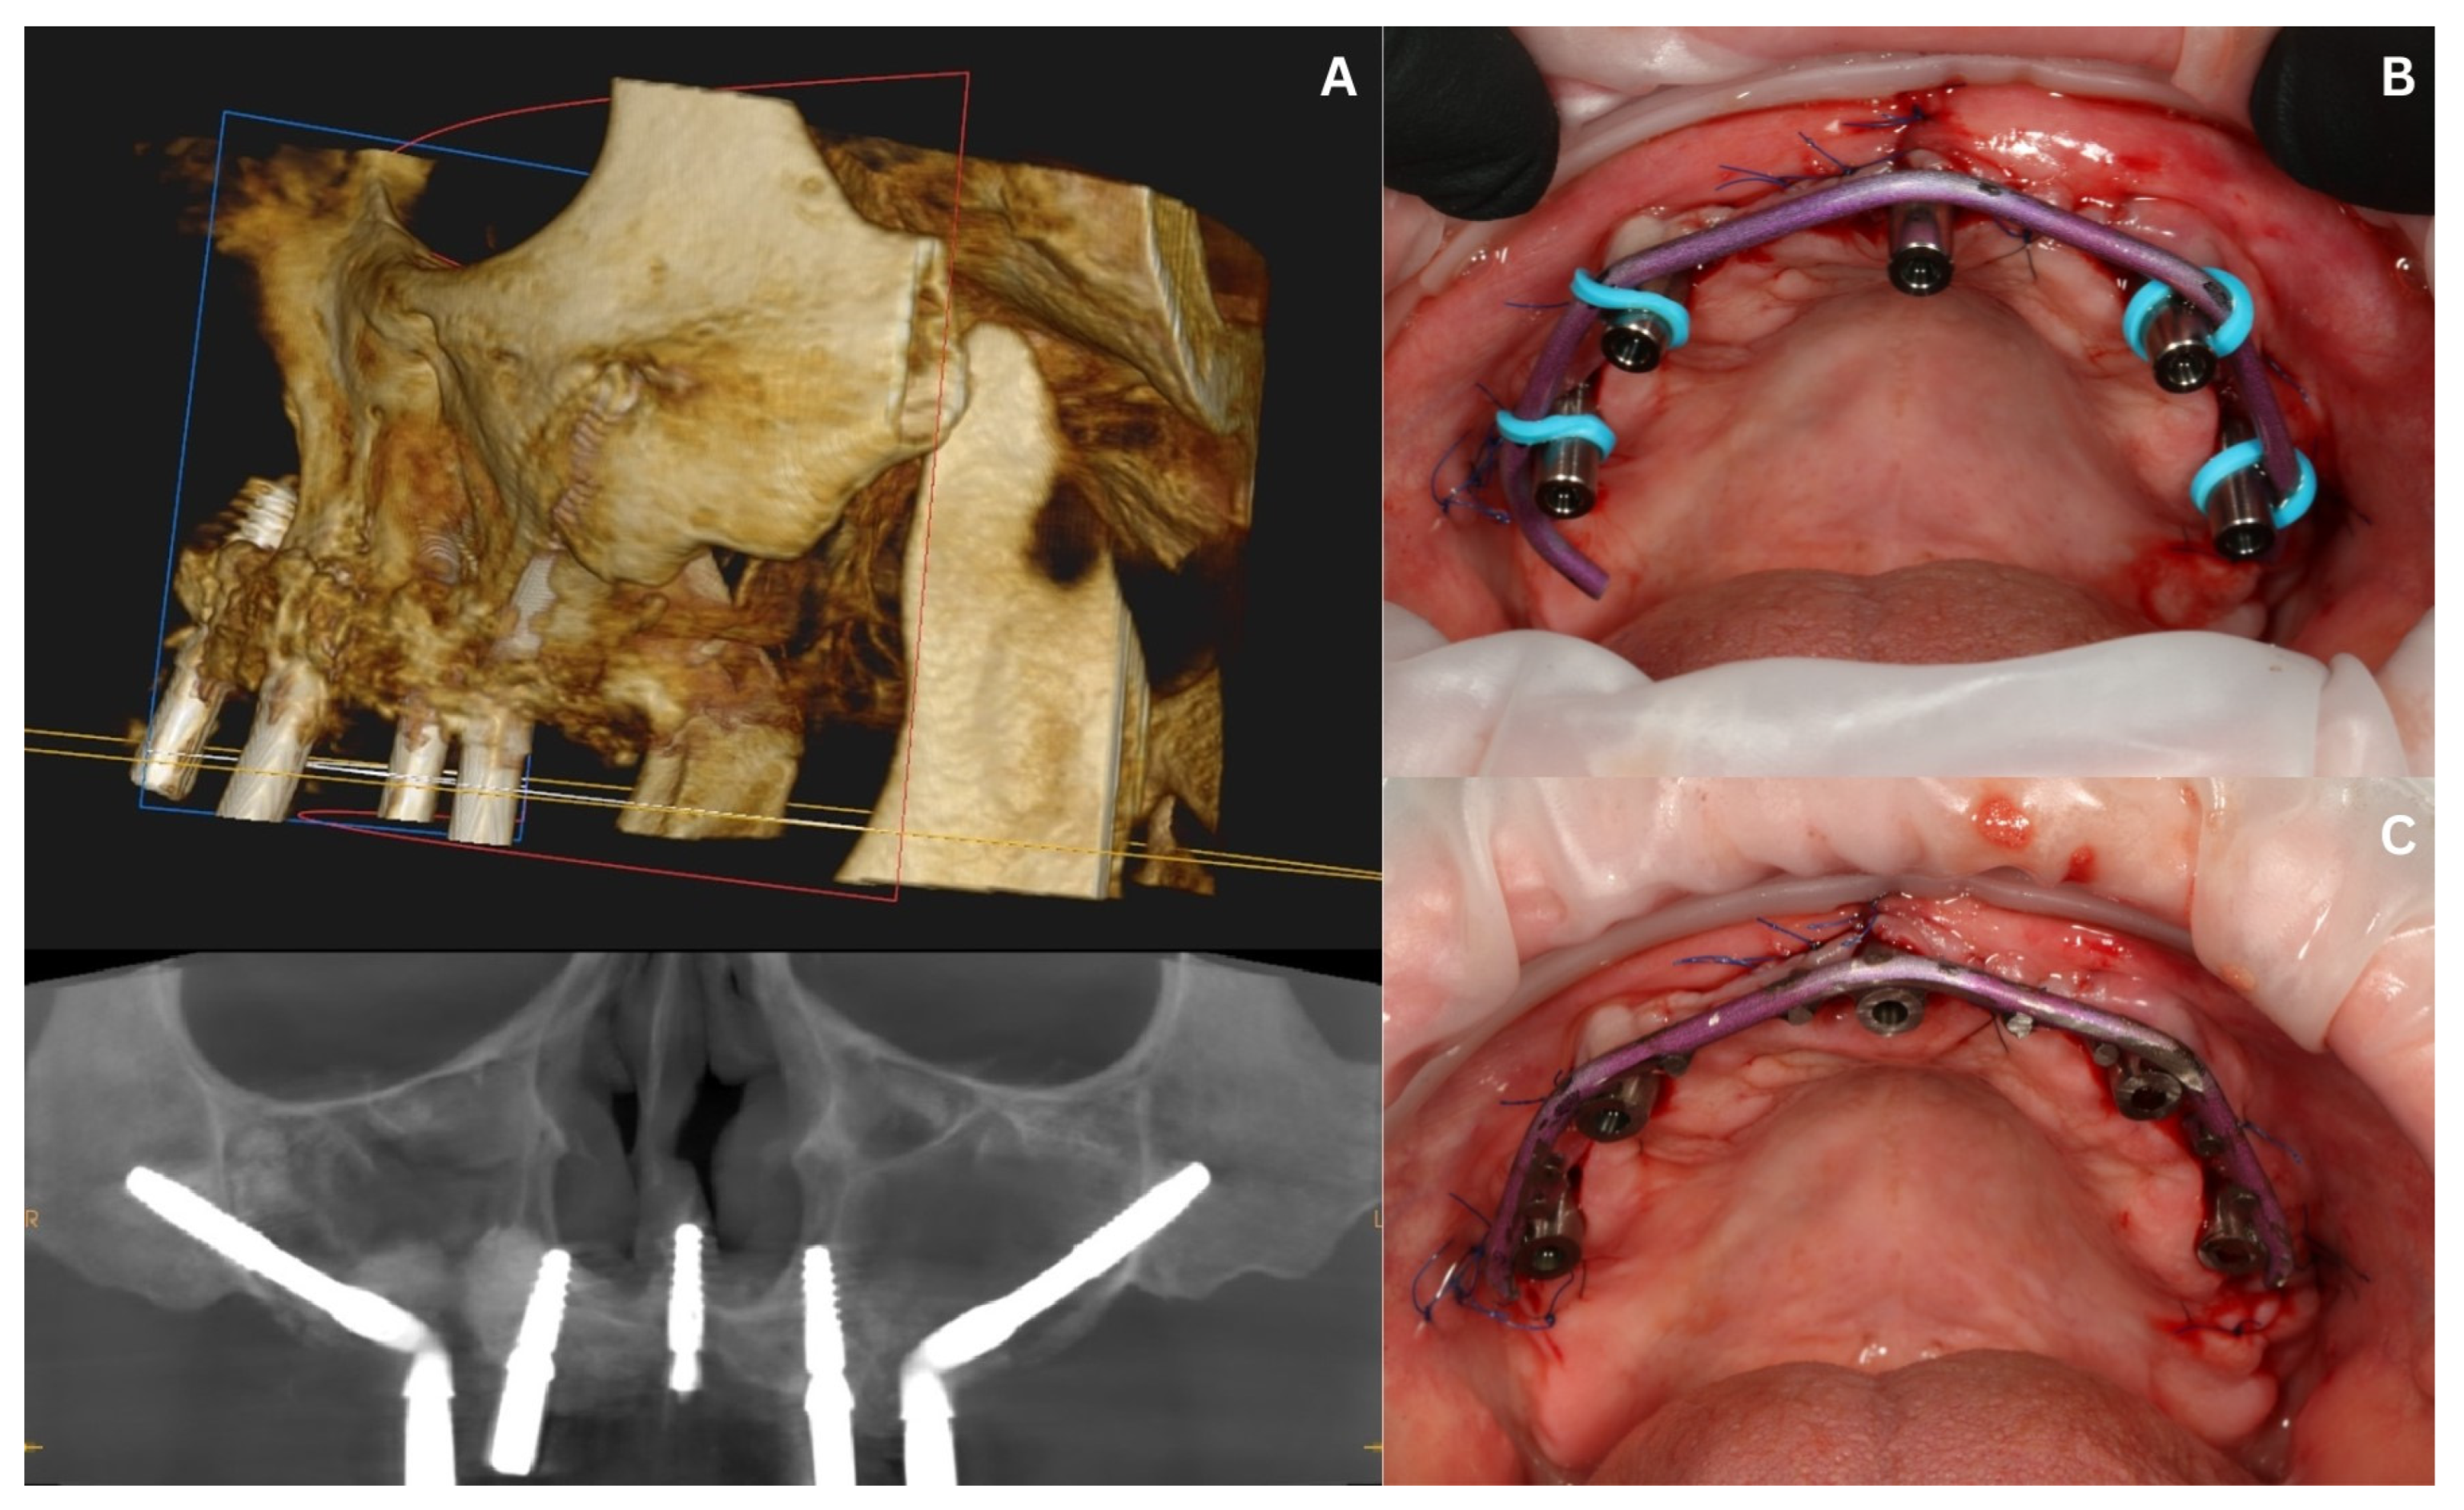

3.3. Surgery in the Maxilla and Immediate Loading—Stage II

2. Patient Information and Clinical Findings